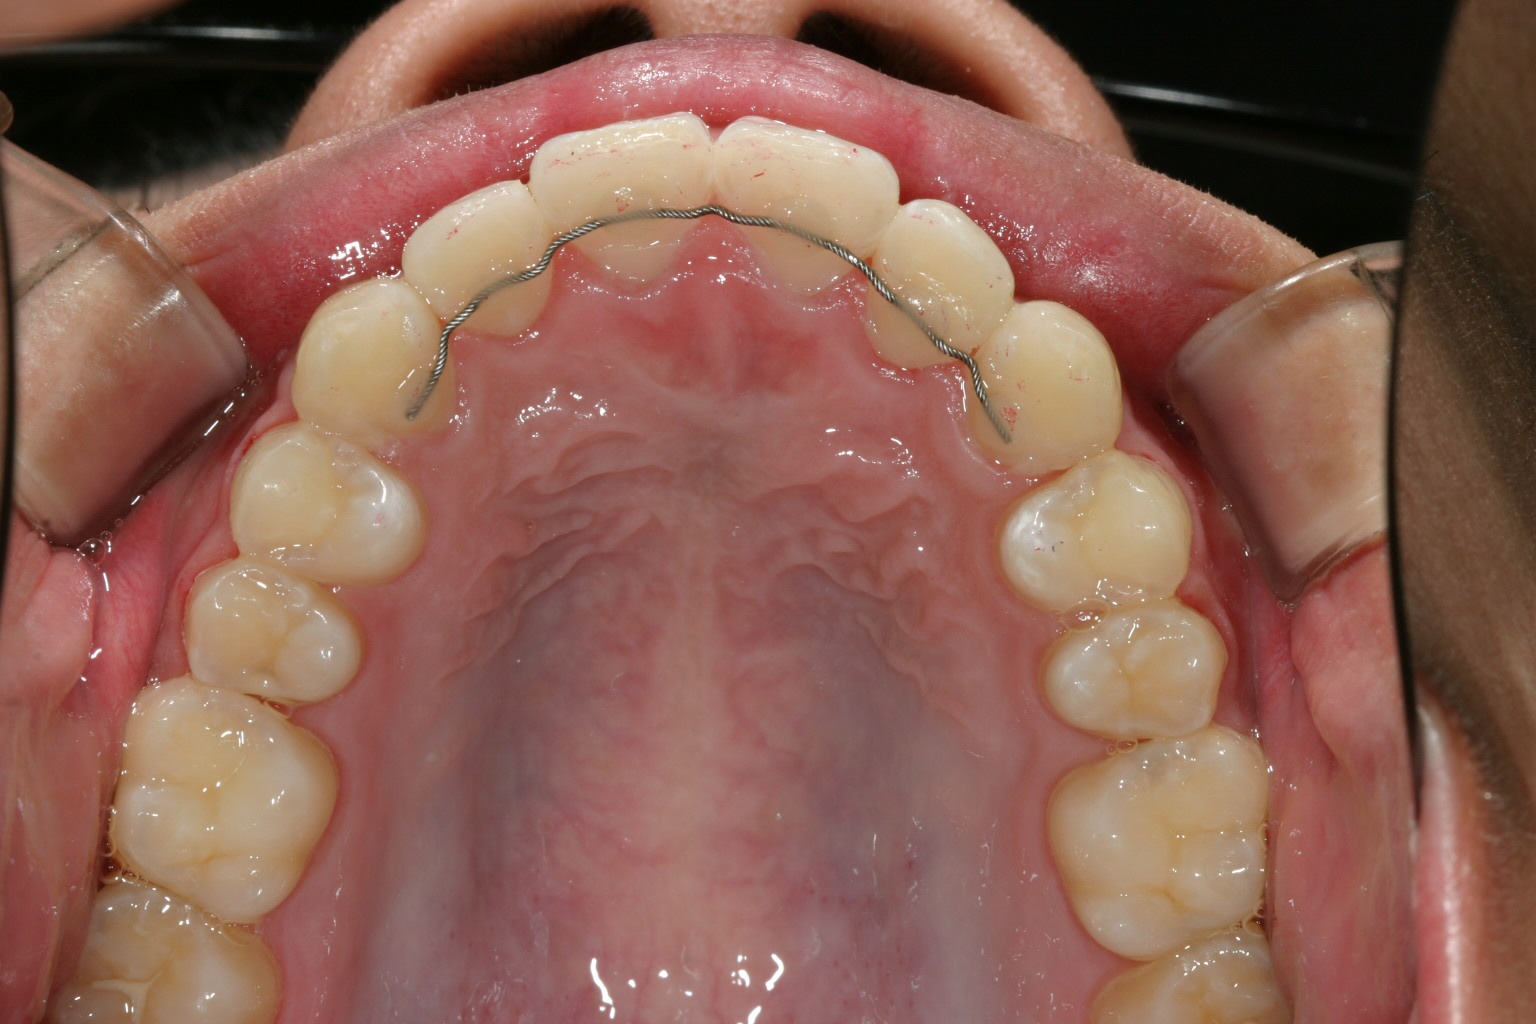

アーチを広げ綺麗に配列しました。

当院ではよくあるケースで犬歯間が狭くなっている為上手く前歯が並んでいません。

と言う事で少しアーチを広げる事によりこの様に綺麗な咬み合わせに改善します。